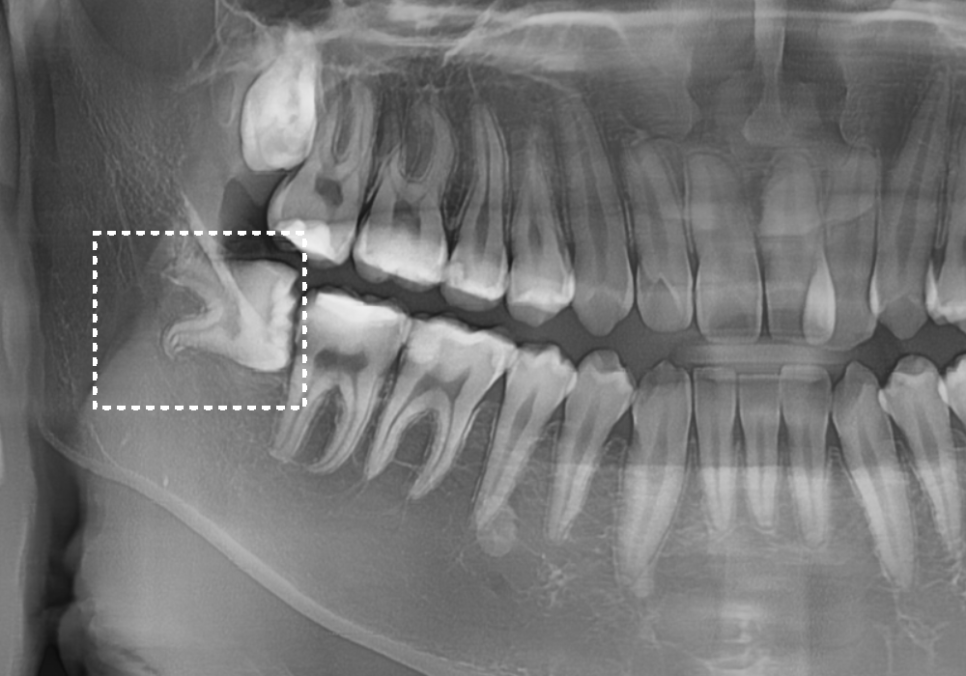

하지만 엑스레이를 찍어보니

상황이 조금 달랐습니다.

사랑니가 앞 치아(#47) 쪽으로

비스듬히 누워 있는 상태였거든요.

여기서 꼭 아셔야 할 점이 있어요.

사랑니가 잇몸 속에 아예 푹 잠겨 있으면

오히려 괜찮습니다.

하지만 아주 조금이라도

잇몸 밖으로 고개를 내밀면,

앞 치아와 사랑니 사이에 좁은 틈이 생기죠.

이 틈은 칫솔질을 아무리 열심히 해도

칫솔이 닿지 않는 '사각지대'가 됩니다.

음식물 찌꺼기와 세균이 머물기

딱 좋은 환경이 되는 거예요.

그래서 잇몸 밖으로 드러난 사랑니는

웬만하면 뽑는 게 좋습니다.